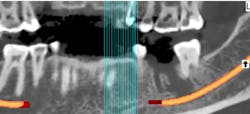

In many cases, removing these lesions in their entirety will increase the risk of canal penetration (figure 2) and subsequent paresthesia (figure 3).

Figure 2: CT scan showing penetration of IAN canal after extraction and socket debridement

In summation, the best treatment for nerve injury continues to be prevention. If there is any doubt by the treating clinician as to the proximity of an odontogenic lesion to the nerve space (figure 4), a CT scan prior to extraction therapy is the gold standard of care (figure 5). This pretreatment diagnostic can avoid both clinical and legal headaches.

Figure 5: Preoperative CT scan obtained prior to tooth extraction to prepare for surgery and limit the possibility of nerve violation